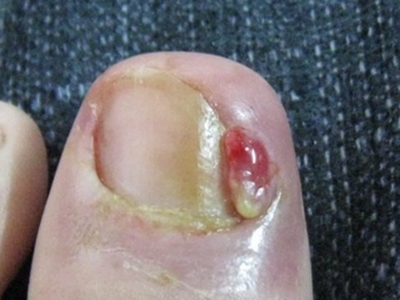

甲床炎患者受到外伤及细菌感染,可使甲床化脓及发炎,以后甲可以扭曲甚至脱落,严重患者的指(趾)头可以溃烂坏死。天疱疮、疱疹样皮炎、剥脱性皮炎、毛发红糠疹、银屑病、梅毒以及甲板下的异物都可引起甲床炎。

甲床炎需根据具体情况进行判断,如果症状较轻,可以听从医生建议,进行热敷,外用抗生素抑制感染。

如果感染已累及甲基部皮下周围,则需要进行手术,将甲根部去除。如果甲床下有脓液,需做拔甲处理。